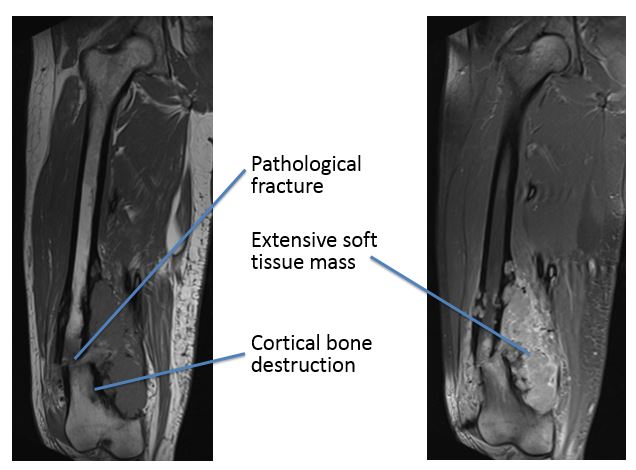

Both a CT scan and an MRI scan confirmed these findings.

In view of the high suspicion of sarcoma, he was referred to the supra-regional sarcoma unit where he had an open biopsy that confirmed the diagnosis of osteosarcoma. About 60% of osteosarcomas affect the knee region, 15% the hip, 10% the shoulder and 8% the jaw.